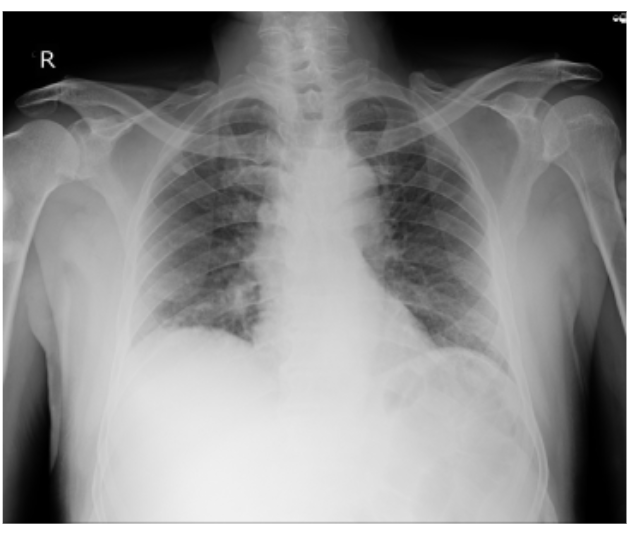

CHEST XRAY - NORMAL

CHEST X RAY: